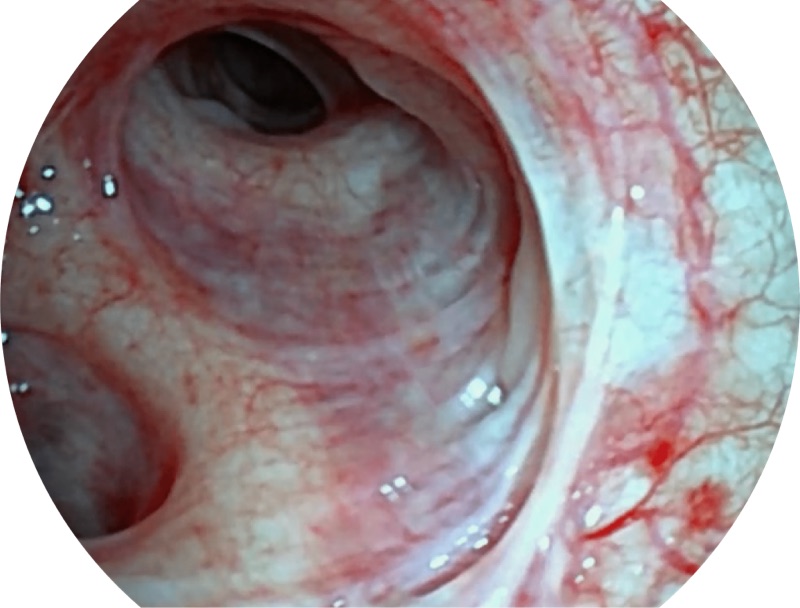

帮助医生更加清晰地观察气管表面病灶

EB-5H20具有4.9mm外径及2.0mm钳道提升对外围支气管检查能力

白光

SFI

VIST